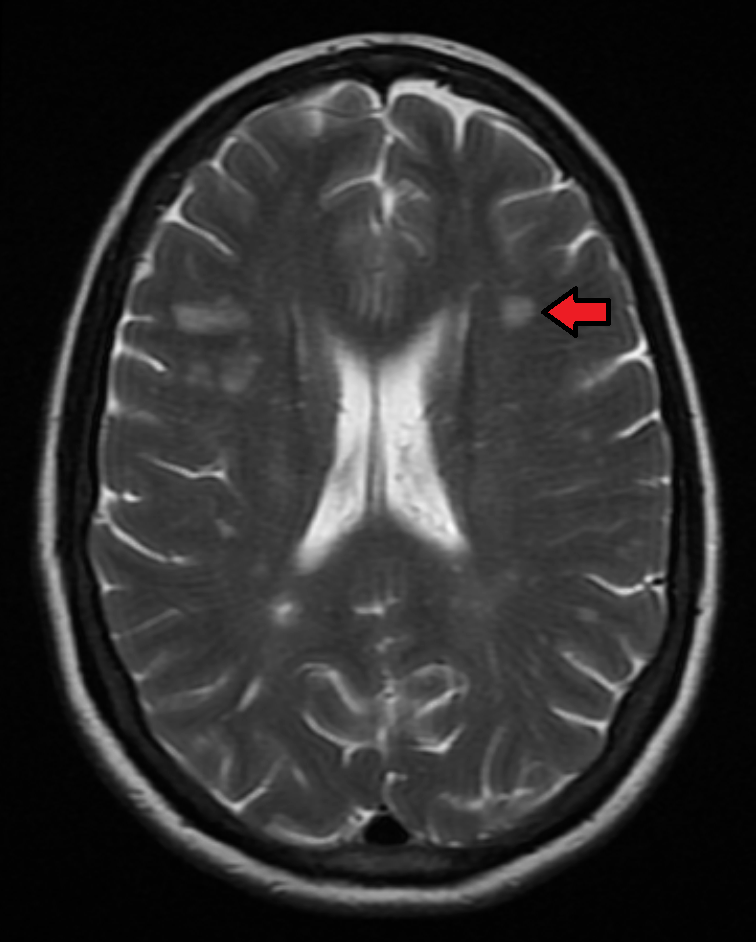

| 이미지 | |

![]() | |

다발성 경화증 진단에는 맥도날드 기준(McDonald Criteria)이 사용되며, 임상적 진단과 함께 자기공명영상(MRI) 결과가 포함된다.[102][107] 뇌 및 척수의 MRI는 탈수초(병변 또는 판) 영역을 보여줄 수 있다. 가돌리늄을 조영제로 사용하여 활성 판을 강조하고, 증상과 관련 없는 과거 병변의 존재를 확인할 수 있다.[102][107]

조영증강 MRI를 추가하면 조기 진단이 가능하다. 무증상 Gd 증강 병변과 비조영 병변이 동시에 관찰되면 1회 MRI 검사로 시간적 다발성(DIT)을 증명할 수 있다. 추적 MRI 검사에서 새로운 T2 강조 병변 또는 Gd 증강 병변이 확인되는 경우에도 DIT를 증명할 수 있다. 공간적 다발성(DIS)에서도 MRI는 중요한 역할을 한다. 뇌실주위, 피질근방, 천막하, 척수의 4영역 중 2개 이상에서 각각 1개 이상의 T2 강조 병변이 확인되면 공간적 다발성을 증명한 것이다. 뇌실주위와 피질근방에 병변이 발생하기 쉽다.

천막상 병변은 T2 강조 영상보다 FLAIR 영상이 우수하지만, 뇌간과 기저핵의 MS 병변은 FLAIR보다 T2 강조 영상이 우수하다. 뇌실에 수직으로 존재하는 타원형 병변인 Dawson's finger는 FLAIR 영상의 시상면에서 가장 잘 확인된다. 병소의 활성도 평가를 위해 조영증강 MRI가 시행되며, open ring sign은 MS에 비교적 특이적이다. 조영증강 병변은 재발-완화형 다발성 경화증(RRMS)에서 많이 나타나고, 진행형 다발성 경화증(PPMS)에서는 적게 나타난다. T2 강조 영상에서 고신호를, T1 강조 영상에서 저신호를 나타내는 병변을 black hole이라고 한다. 시신경염을 의심할 때 관상면 MRI에서 지방억제 T2 강조 영상으로 시신경이 고신호로 나타나는 경우가 있으며, 지방억제 Gd T1 강조 영상을 촬영하기도 한다.

다발성 경화증 진단에는 맥도날드 기준(McDonald Criteria)이 사용되며, 임상적 진단과 함께 자기공명영상(MRI) 결과가 포함된다.[102][107] 뇌 및 척수의 MRI는 탈수초(병변 또는 판) 영역을 보여줄 수 있다. 가돌리늄을 조영제로 사용하여 활성 판을 강조하고, 증상과 관련 없는 과거 병변의 존재를 확인할 수 있다.[102][107]조영증강 MRI를 추가하면 조기 진단이 가능하다. 무증상 Gd 증강 병변과 비조영 병변이 동시에 관찰되면 1회 MRI 검사로 시간적 다발성(DIT)을 증명할 수 있다. 추적 MRI 검사에서 새로운 T2 강조 병변 또는 Gd 증강 병변이 확인되는 경우에도 DIT를 증명할 수 있다. 공간적 다발성(DIS)에서도 MRI는 중요한 역할을 한다. 뇌실주위, 피질근방, 천막하, 척수의 4영역 중 2개 이상에서 각각 1개 이상의 T2 강조 병변이 확인되면 공간적 다발성을 증명한 것이다. 뇌실주위와 피질근방에 병변이 발생하기 쉽다.